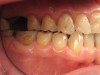

Figure 8 and Figure 9 The right and left side preoperative retracted mirror views.

Figure 8

Figure 9

When viewing his maxillary teeth from an occlusal and lingual view, one can see the erosion and wear (Figure 4, Figure 6, and Figure 7), and it becomes evident just how collapsed he actually is. This patient shows more teeth on his left side and less on the right when smiling, and the shortness and color of his teeth contributes to a definite aging of his smile. Additionally, his lips appear less full without the lip support of the lost tooth structure. The patient had Class I molar relationships on both the right and left sides, and a posterior open bite on his right side in the area of teeth Nos. 4 through 6 (Figure 8 and Figure 9). There was no crowding evident and both arches were found to have lingually inclined teeth, which may have contributed to his wear. It was also noted that his posterior teeth were worn down with a very flat anatomy and lacked proper functional guidance.